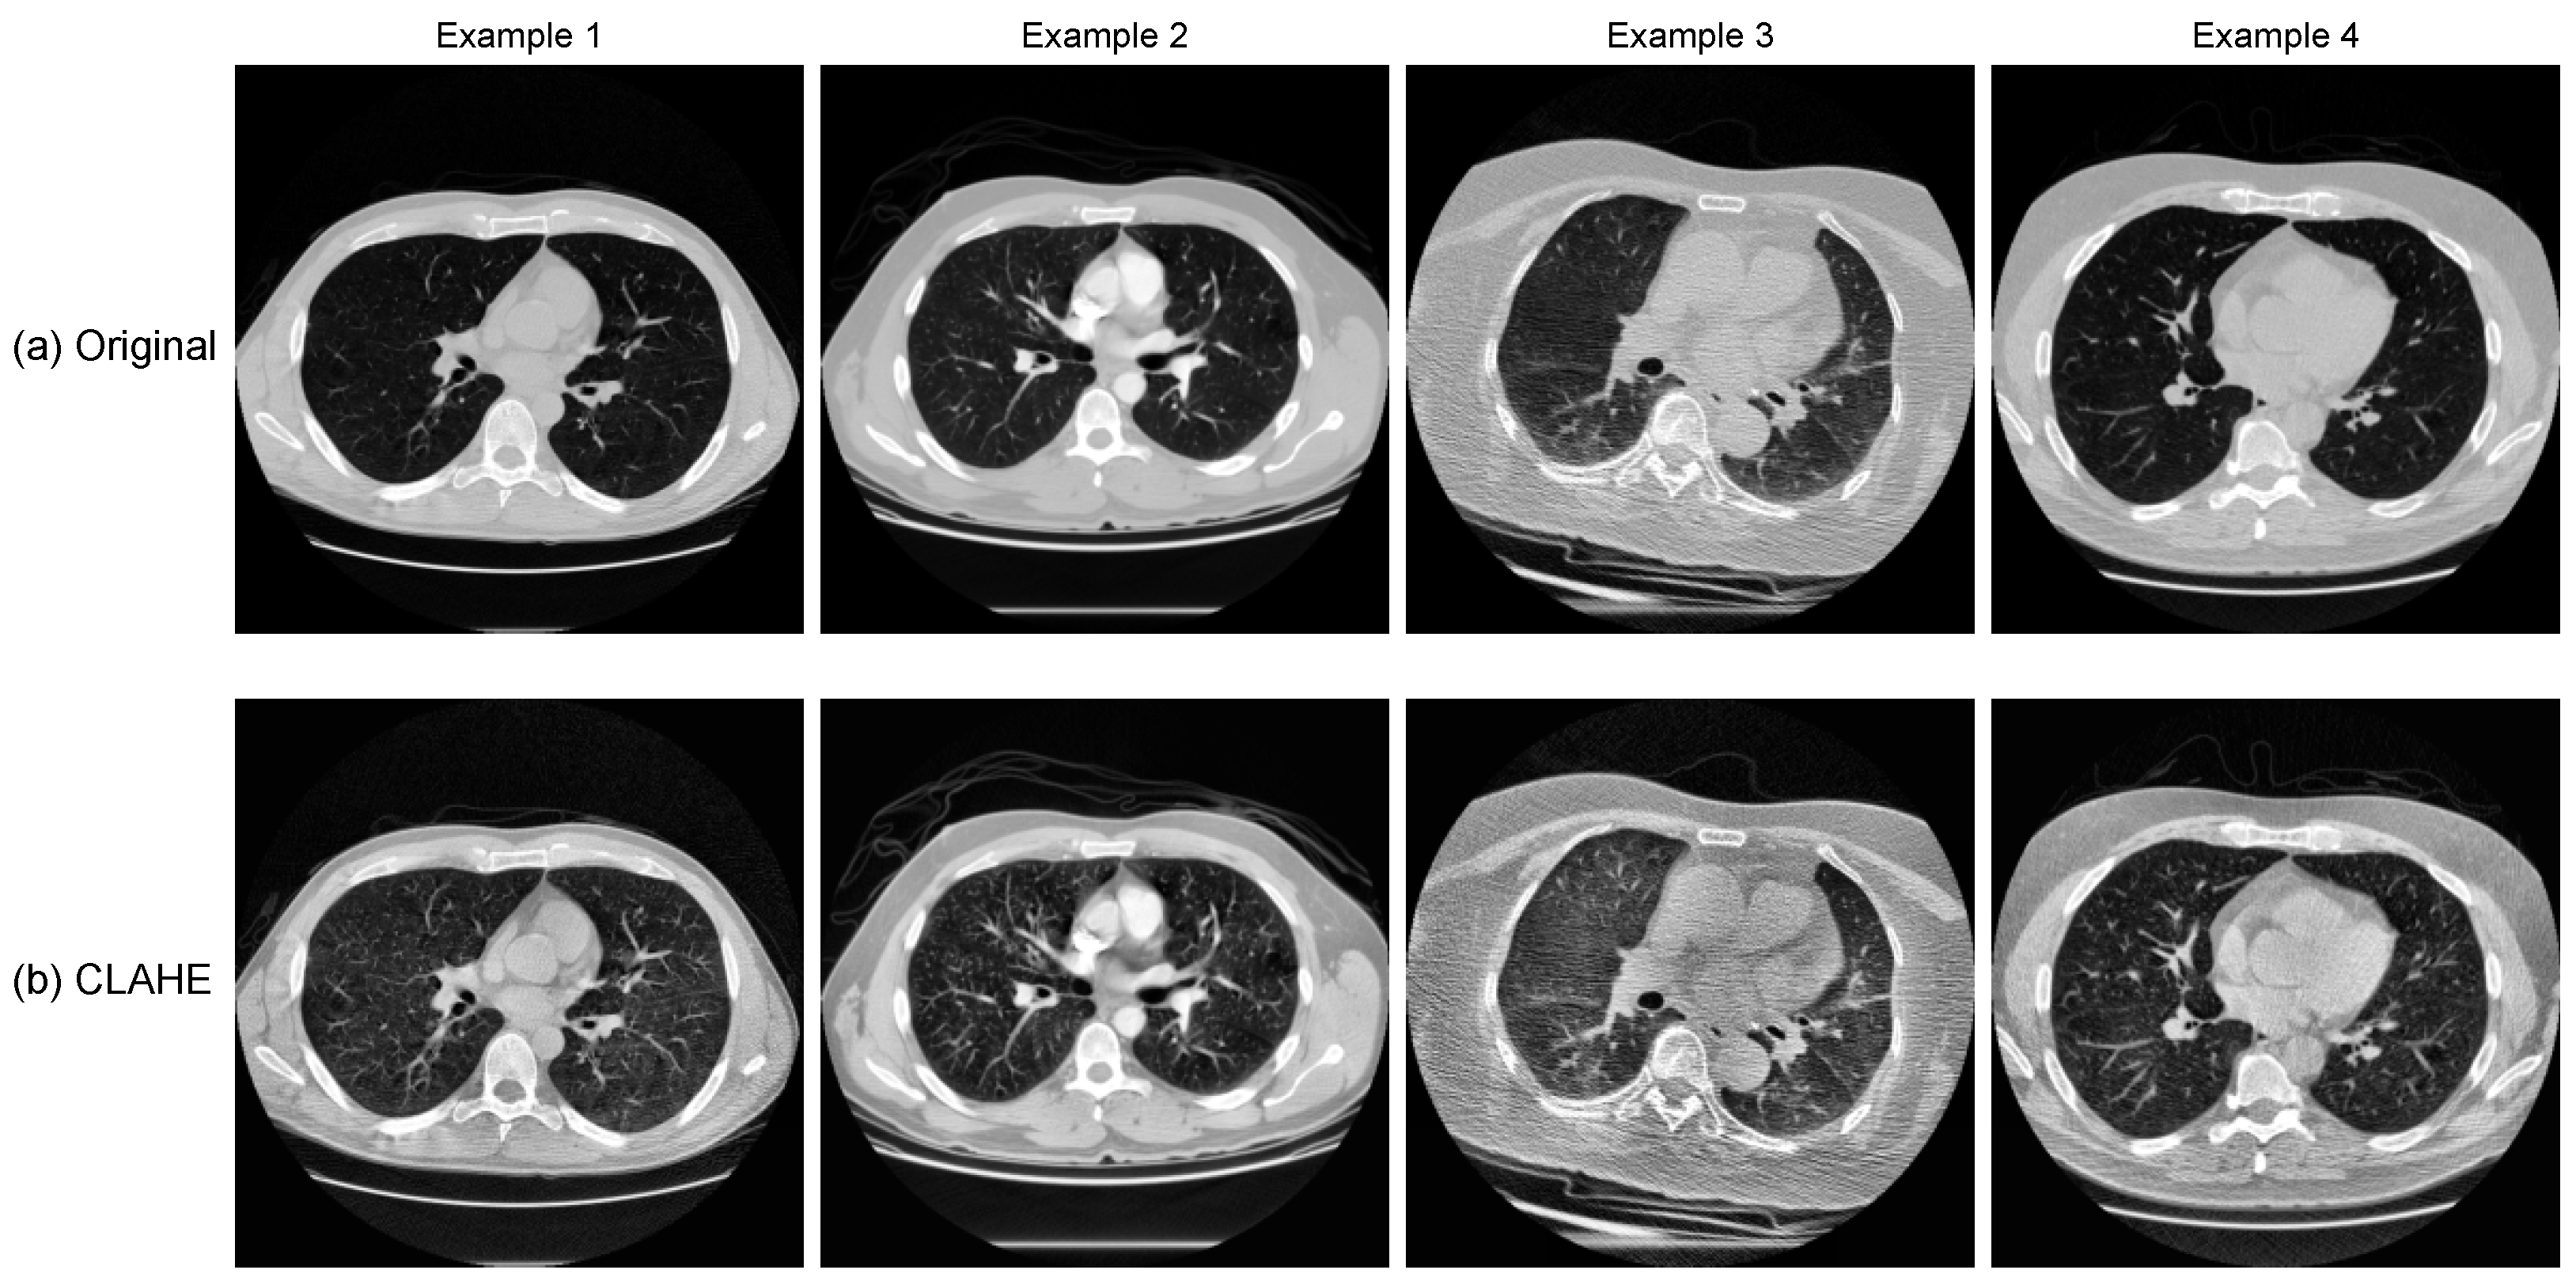

- A data pipeline tailored for LUNA16 (HU normalisation, CLAHE enhancement, lung masking, and slice-level packaging) for stable 2.5D inputs;

4.1. Image Enhancement and Quality Assessment

4.2. Preprocessing Visualisation